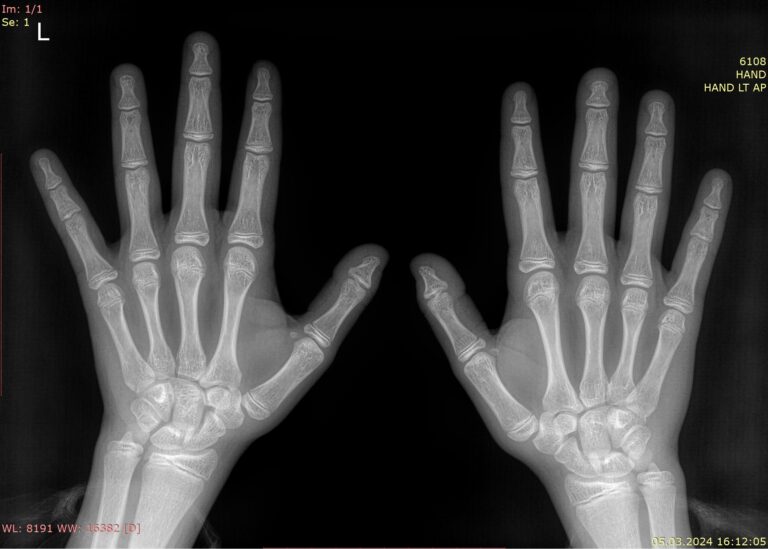

Методика определения костного возраста ребенка основана на знании процесса окостенения запястья и костей кисти. При рождении большинство костей запястья состоят из хрящевой ткани, постепенно они окостеневают. На пястных костях и фалангах образуются и затем также костенеют эпифизы ― концы трубчатых костей. Все костные образования хорошо видны на рентгене.

Готовый снимок рентгенолог сравнивает со стандартными снимками рук детей по рентгенографическим атласам. В них приведены серии снимков начиная с самого раннего возраста.Снимки у мальчиков и девочек различаются. В атласах описываются:

• Размер, форма, плотность, морфология центров окостенения у здоровых детей;

• Уровень образования синостоза ― нормального сращения костной ткани;

• Соотношение костей, суставов и мягких тканей запястья и костей кисти.

В заключении врач указывает приблизительный костный возраст ребенка в годах плюс-минус 6 или 12 месяцев от этапов взросления.